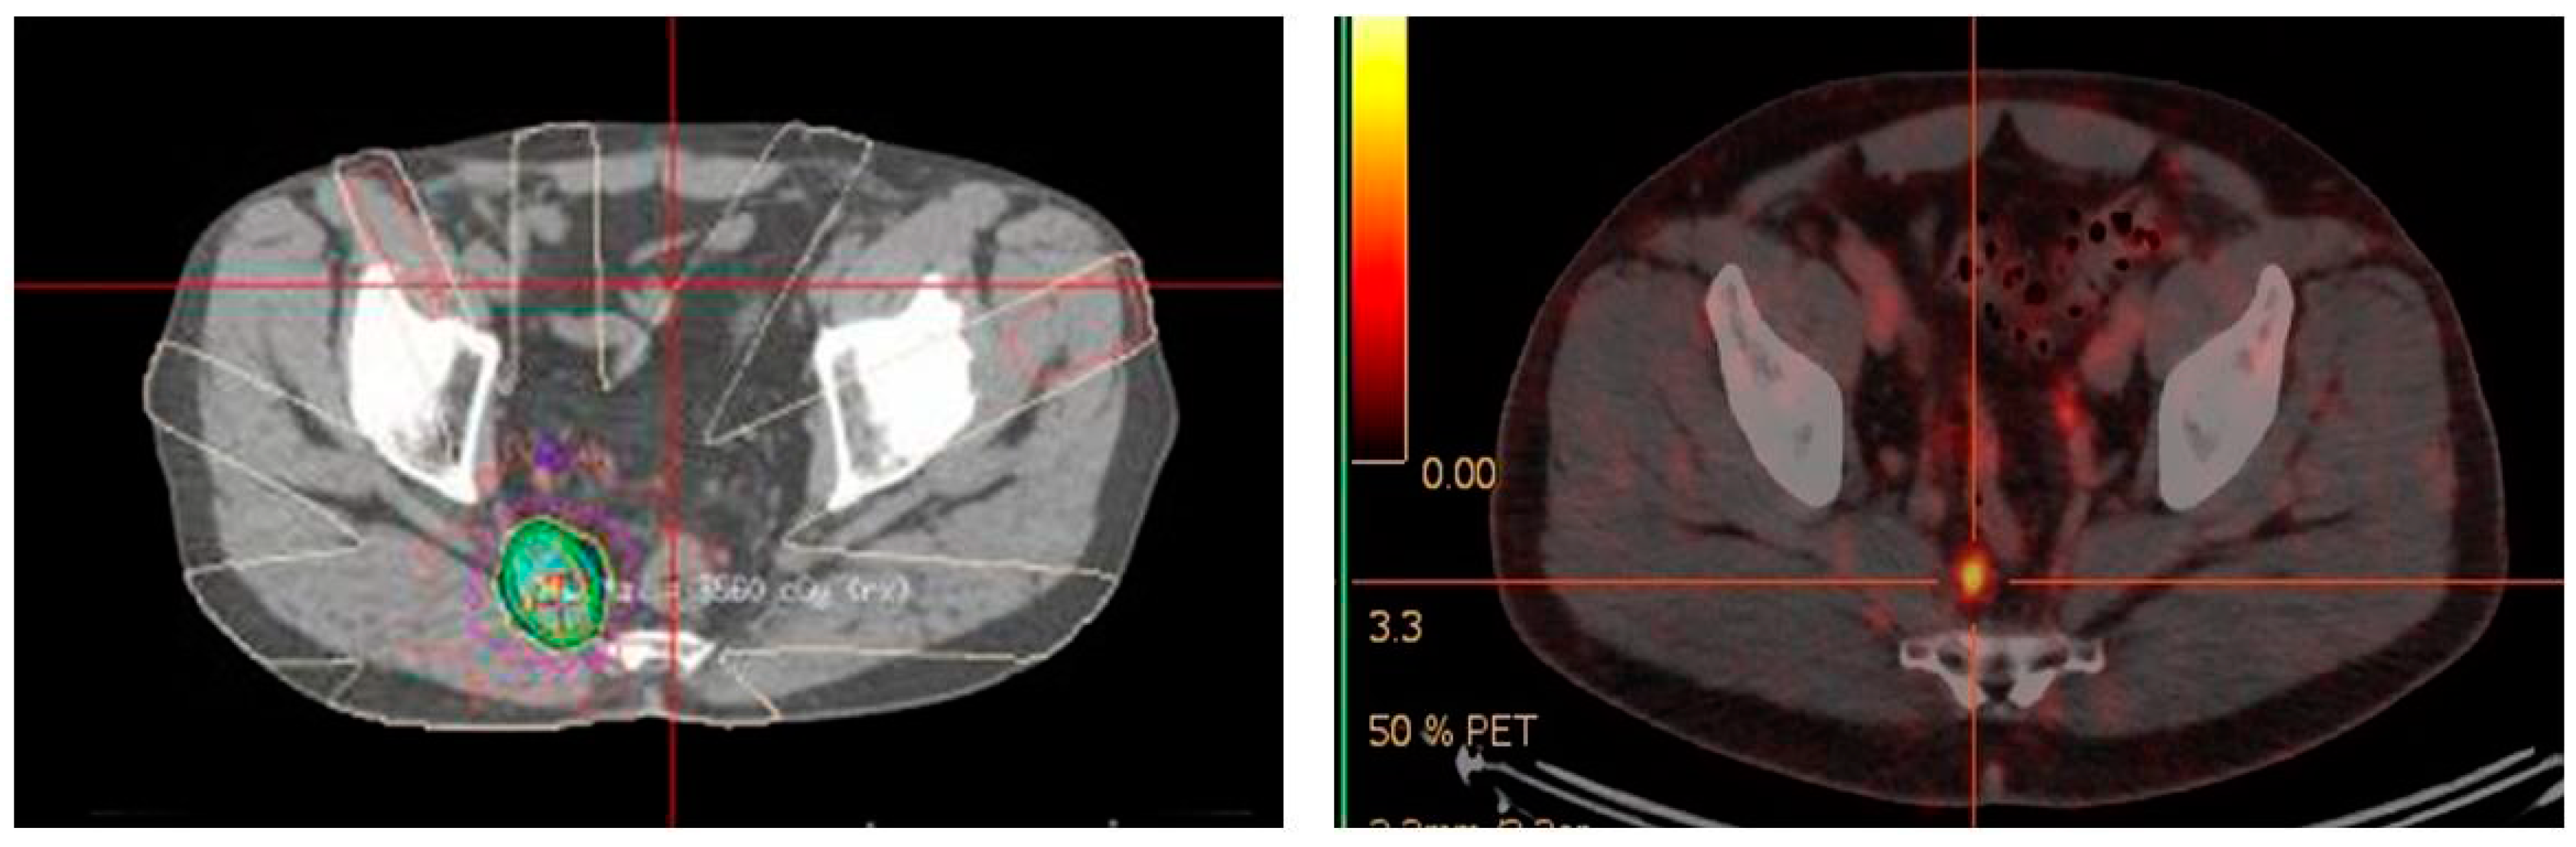

The results with 68Ga-PSMA PET/CT directed external beam radiotherapy in the primary and salvage setting have been encouraging. Several studies have shown a change in radiotherapy planning from 20–60% of patients imaged with 68Ga-PSMA PET/CT prior to external beam radiotherapy [93,94,95]. 68Ga-PSMA PET/CT also has a role post-definitive radiotherapy in detecting site of biochemical relapse. In an Australian study of 419 men treated with external beam radiotherapy, 68Ga-PSMA PET/CT identified all cases of biochemical relapse [96]. This allows potential salvage therapy if the recurrence is outside the previous radiotherapy field, as was the case for the patient in Figure 4. A negative 68Ga-PSMA PET/CT scan in the setting of biochemical recurrence also appears to have prognostic implications for salvage radiotherapy. In a study of 164 Australian men, a negative 68Ga-PSMA PET/CT showed treatment response benefit compared with patients with a positive 68Ga-PSMA PET/CT scan [97]. Although seemingly counter-intuitive, this again reinforces the likely scenario that very small volume/micro-metastatic nodal recurrence is more likely to be amenable to pelvic radiotherapy than disease that is visible on 68Ga-PSMA PET/CT. By this stage the chance of disease having spread outside the confines of the area of the salvage pelvic radiotherapy field, is likely to be high. Whether systemic therapy, combined with either chemotherapy or targeted radiopeptide therapy, together with salvage pelvic radiotherapy can improve response rates in this setting has yet to be elucidated. The long-term outcome of altering treatment planning based on 68Ga-PSMA PET/CT has not yet been addressed in any large longitudinal studies.

Figure 4.

Targeted radiotherapy to recurrent 68Ga-PSMA avid right pre-sacral lymph node. June 2015.

4.3. Monitoring Treatment Response

Serial 68Ga-PSMA PET/CT scans have been used to assess the intermediate term outcomes of radiotherapy in recurrent nodal disease [98,99] (Figure 5). These studies show reductions in SUV in most lesions treated, indicating response, however, the responses based on 68Ga-PSMA PET/CT may take several months to be fully realized [99]. Therapeutic response of chemotherapy based on 68Ga-PSMA PET/CT imaging has been poorly studied with only a single paper showing a potential role of this imaging modality with monitoring the effectiveness of docetaxel chemotherapy [100]. This is, however, a growing area of interest as 68Ga-PSMA PET/CT imaging starts taking over the traditional role that CT and bone scintigraphy has had in monitoring chemotherapeutic response in prostate cancer patients [27]. The poor correlation of RECIST to recognized measures of evaluating molecular responses to cancer treatments, such as the European Organization for Research and Treatment of Cancer (EORTC) criteria has been documented [101]. There is a consensus movement within the nuclear medicine community to harmonize quantitative methods to more accurately compare tumor response to treatment, such as with standard uptake values, and using established criteria such as those found in the EORTC [102], and the PERCIST criteria [103]. More specific definitions for interpreting and evaluating responses 68Ga-PSMA PET/CT have also been described [104]. These molecular based evaluation systems will likely replace the antiquated RECIST criteria for assessing therapeutic response in the era of targeted therapies and molecular imaging.

Figure 5.

Monitoring response of targeted radiotherapy by 68Ga-PSMA PET/CT August 2016. (Previous 68Ga-PSMA avid right pre-sacral lymph node treated June 2015—see Figure 4).